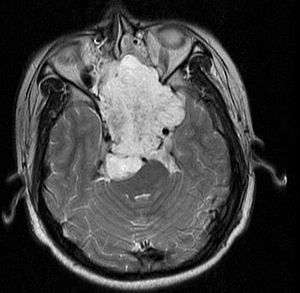

MRI of extensive clival chordoma in 17-year-old male patient, axial view. Tumor in the nasopharynx extending from nasal cavity to brainstem posteriorly is clearly visible. | |

Chordomas can arise from bone in the skull base and anywhere along the spine. The two most common locations are cranially at the clivus and in the sacrum at the bottom of the spine.[1]